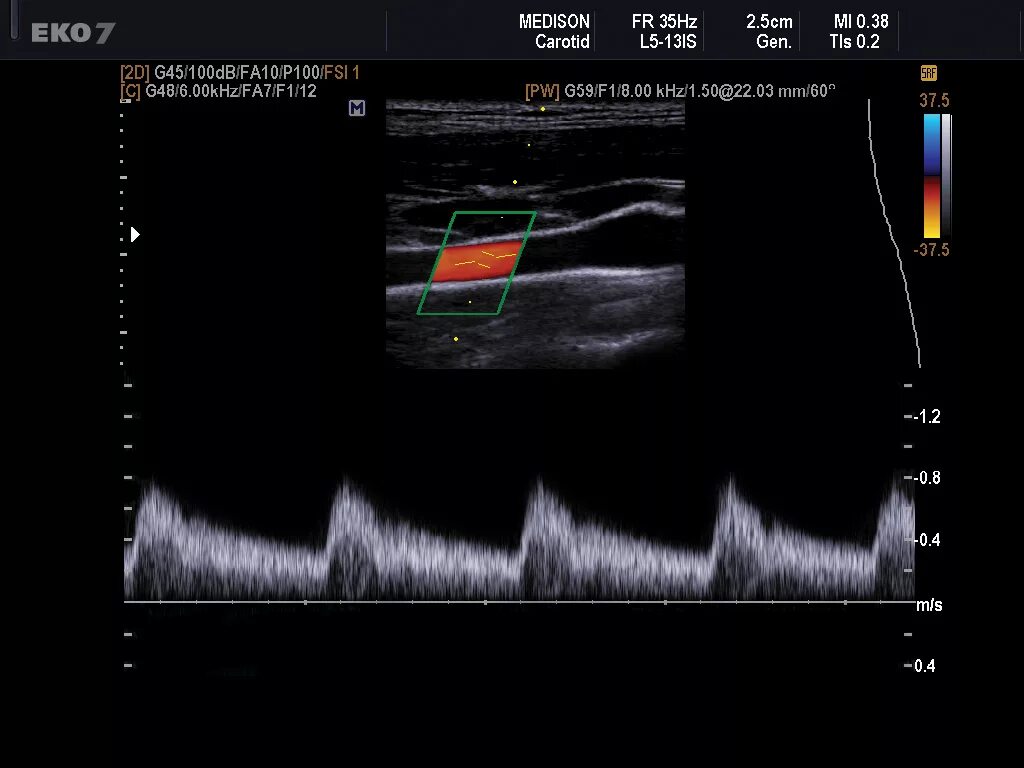

Сделать узи сонной артерии